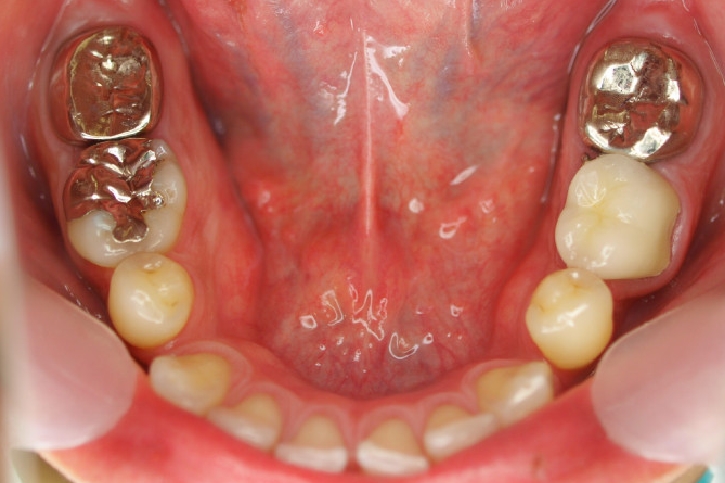

ゴールド修復

担当歯科医師:丸林浩太郎

2013年2月5日千葉市中央区 T.S様 左右6番ゴールドインレー・クラウン修復